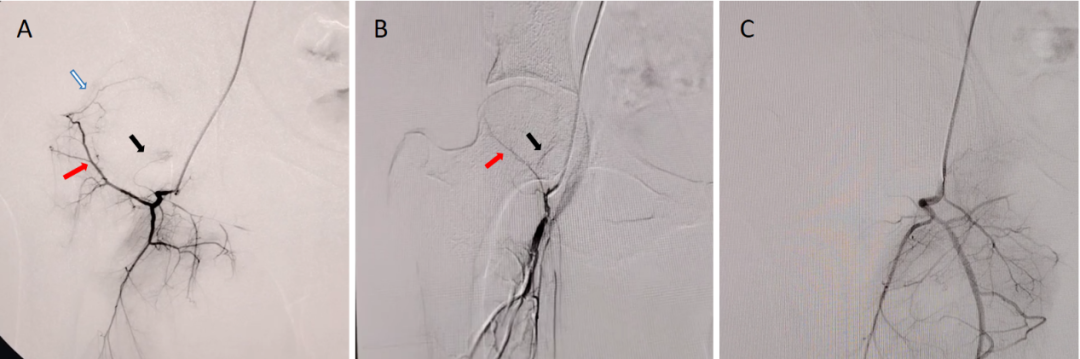

除了常规评估股骨头坏死的分期分型外,科室通过近30年的临床经验的积累,对于股骨头坏死进行数字减影血管造影(digital subtraction angiography, DSA),根据血管的分支情况进行不同的分型,来评估坏死股骨头的血运状态,为精准治疗方案的选择及预后预测提供客观依据。

图A可见旋股内动脉(红色箭头)、上支持带动脉(白色箭头)与下支持带动脉(黑色箭头)均显影,表明股骨头血运状态良好;图B可见旋股内动脉显影较淡薄(红色箭头),上支持带动脉未显影,仅下支持带动脉显影(黑色粗箭头),表明血运状态一般;图C.旋股内动脉及上、下支持带动脉均未显影,表明股骨头血运状态较差。